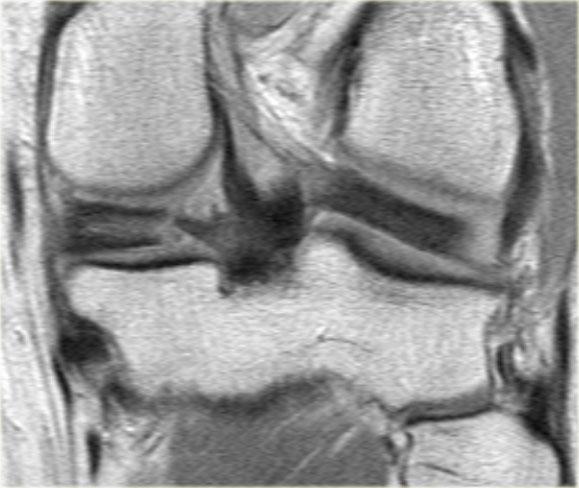

Bên trái là ba lát cắt coronal PD liên tiếp:

-

Rách bó dây chằng bên trong sâu (mũi tên vàng).

Bong mảnh xương ở mặt ngoài đầu gần xương chày, tức là gãy xương Segond (mũi tên đỏ). -

Lưu ý mảnh sụn chêm phía trong bị di lệch.

Điều này cho thấy còn có thêm rách dạng quai xô (bucket handle tear). -

Ngoài rách dạng quai xô (mũi tên xanh phía trong), còn có một đường rách ngang khó nhận thấy ở phần ngoại vi của sụn chêm (mũi tên xanh phía ngoài).

Đường rách ngang này được thể hiện rõ hơn trên các hình ảnh khác (không trình bày ở đây).